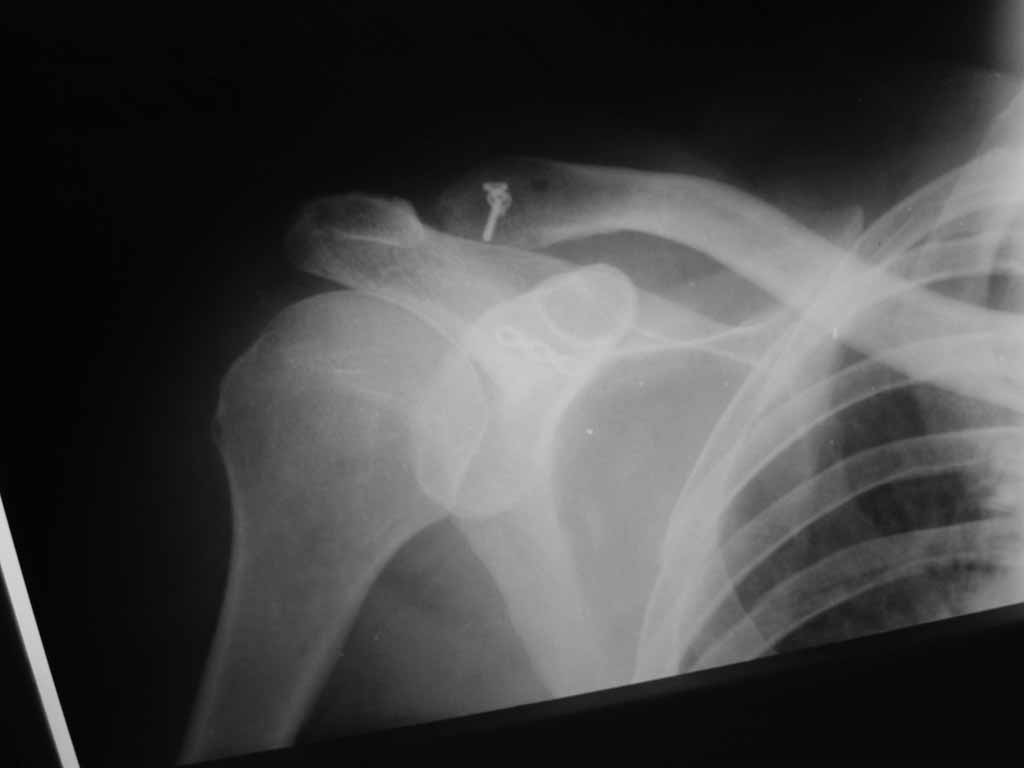

Re: Лечение вывиха акромиального конца ключицы

Используем преимущественно методики реконструкции как клювовидно-ключичной так и акромиально-ключичной связок.

В свежих случаях это наша модификация методики MINAR,или неслолько вариантов лавсанопластики по Беннелю, Бому, Скоблину.

В застарелых случаях реконструкция связок, как правило, дополняется открытым вправлением и резекцией дистального конца ключицы.

MINAR внедрили только в этом году, методика интересная, к настоящему моменту выполнено всего только 9 операций. Однако все результаты были расценены как хорошие. С ув. ЛОКБ, Луганск.